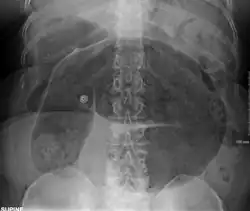

- Abdominal x-ray – tire-like shadow arising from the right iliac fossa and passing to the left

Coffee bean sign in a person with sigmoid volvulus -

An x-ray of a person with a small bowel volvulus.

Plain X ray of a cecal volvulus -